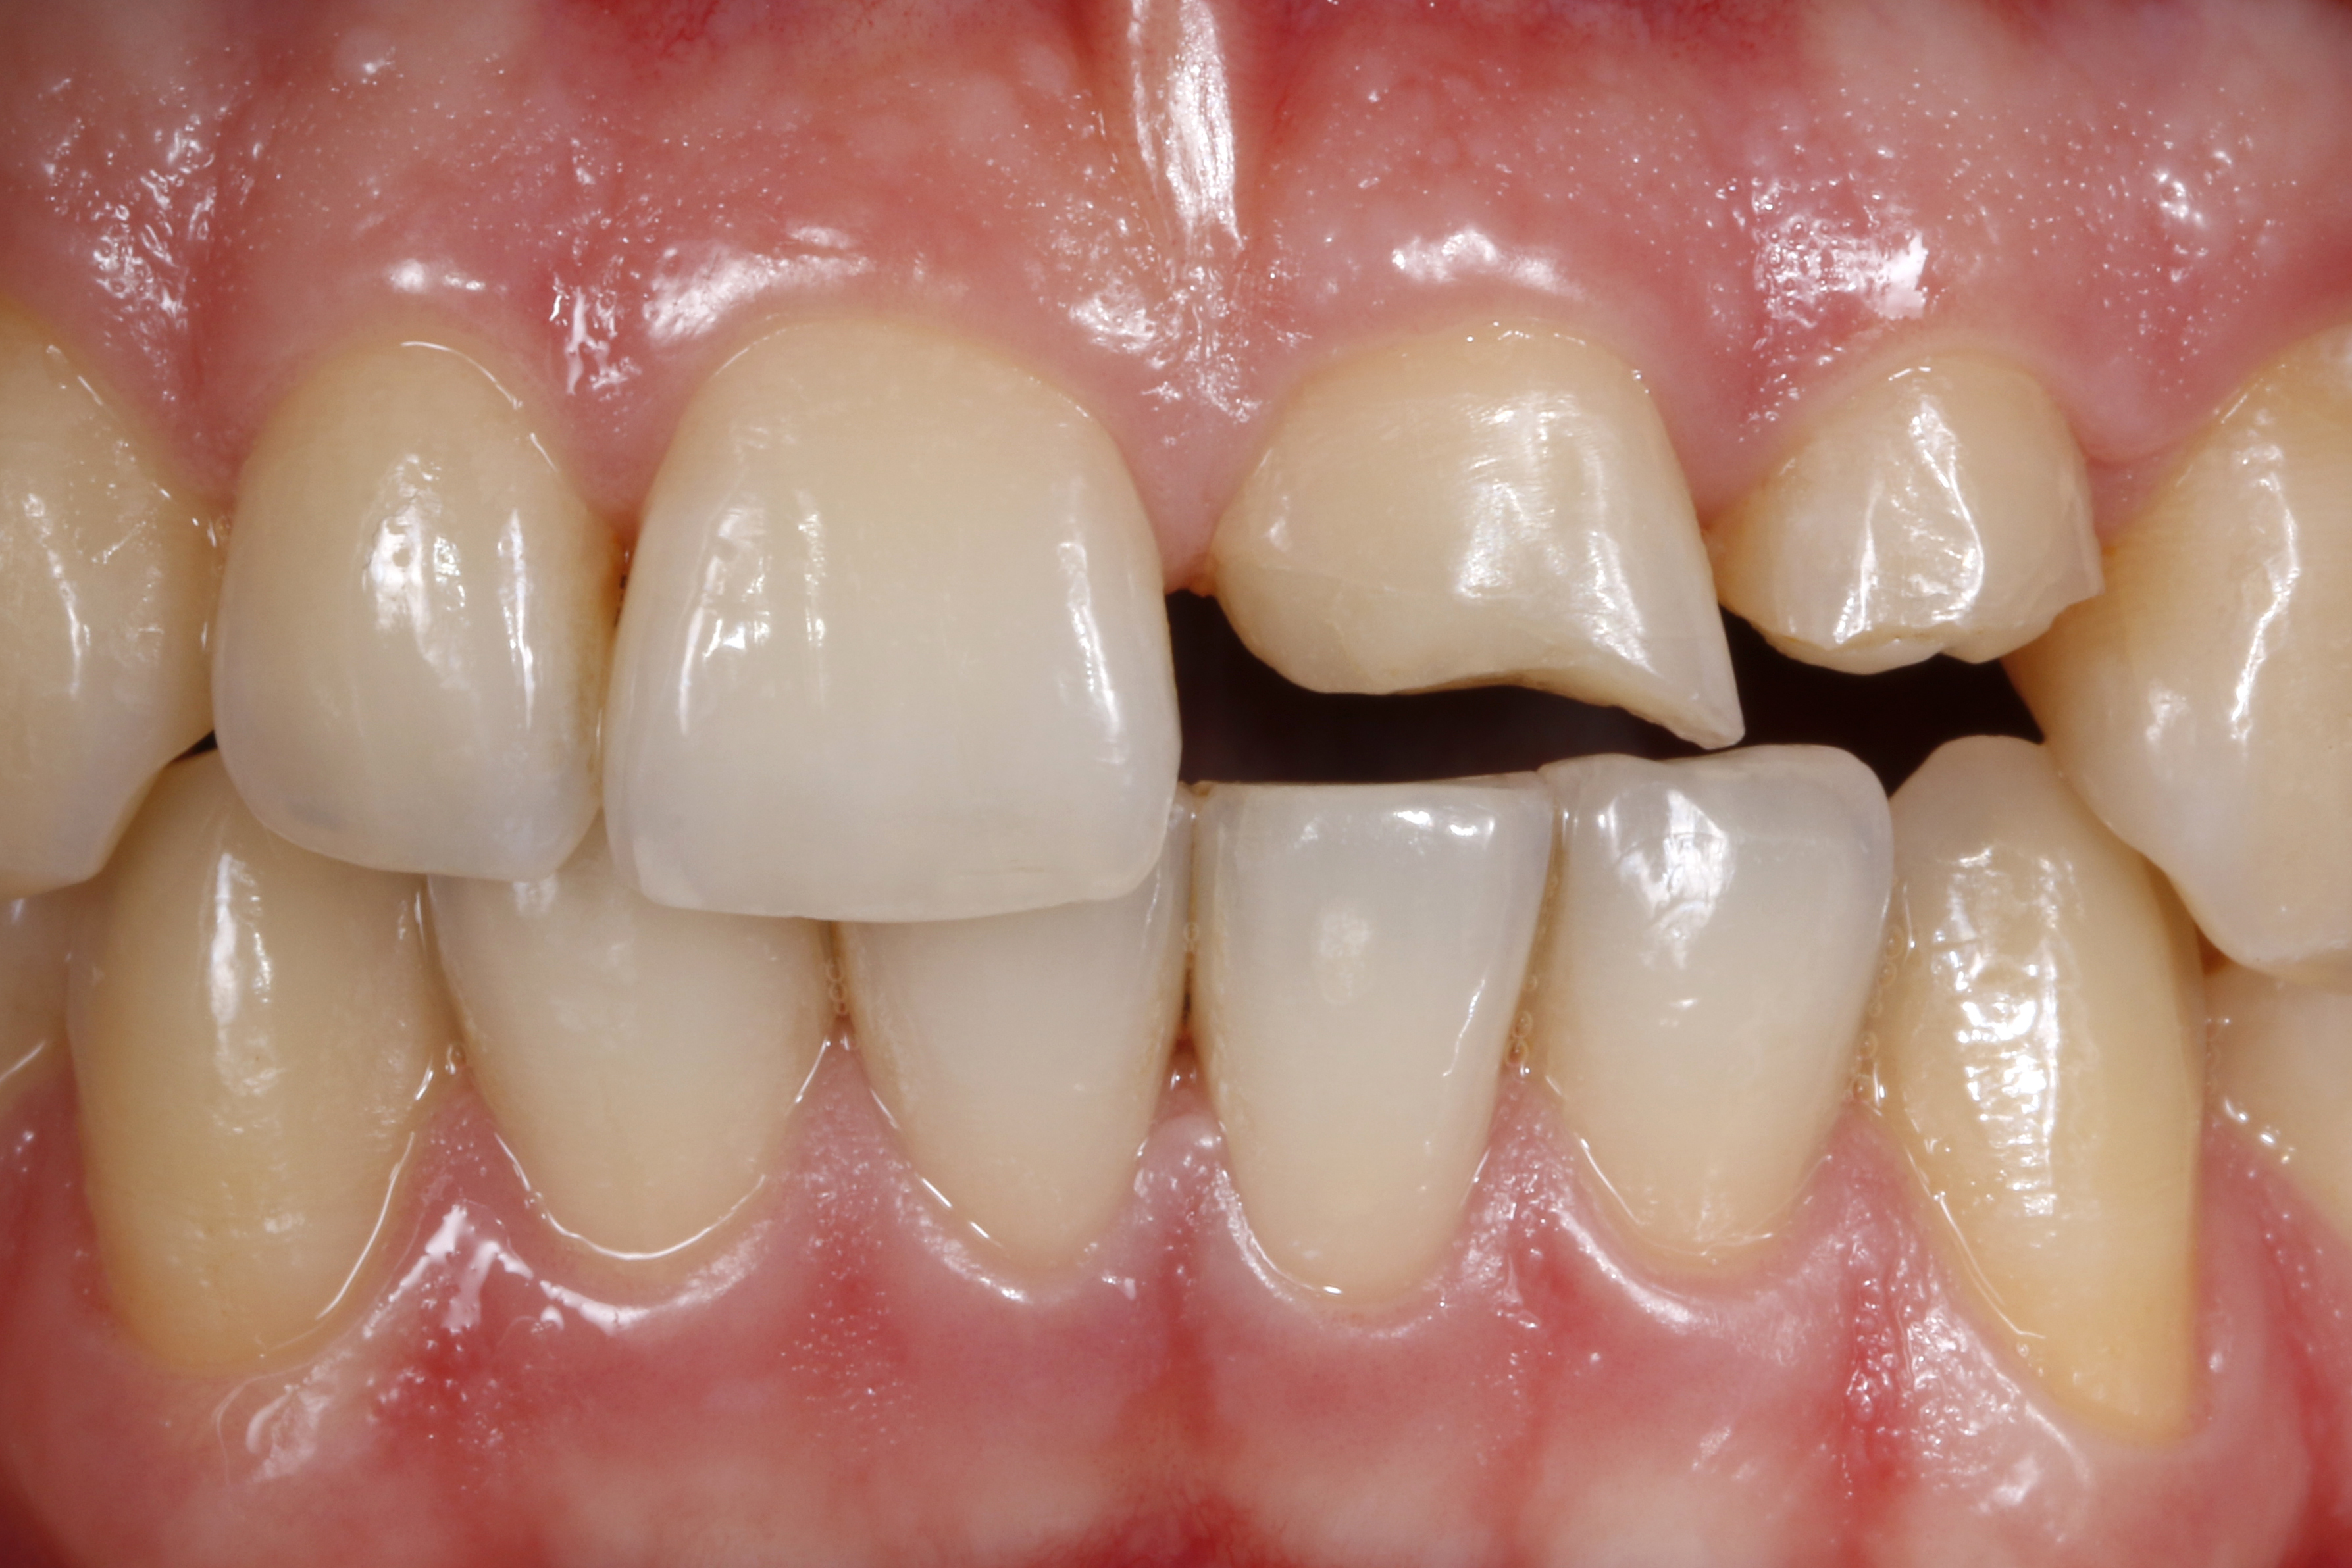

Rozpoznanie - złamanie zębów 21 i 22 na skutek urazu.

Ryc. 1. Sytuacja początkowa – złamane zęby sieczne szczęki po stronie lewej po urazie. Ząb 21 poddano leczeniu endodontycznemu. W zębie 21 przeprowadzono trepanację, do kanału korzeniowego wprowadzono jako tymczasowe zaopatrzenie wodorotlenek wapnia.